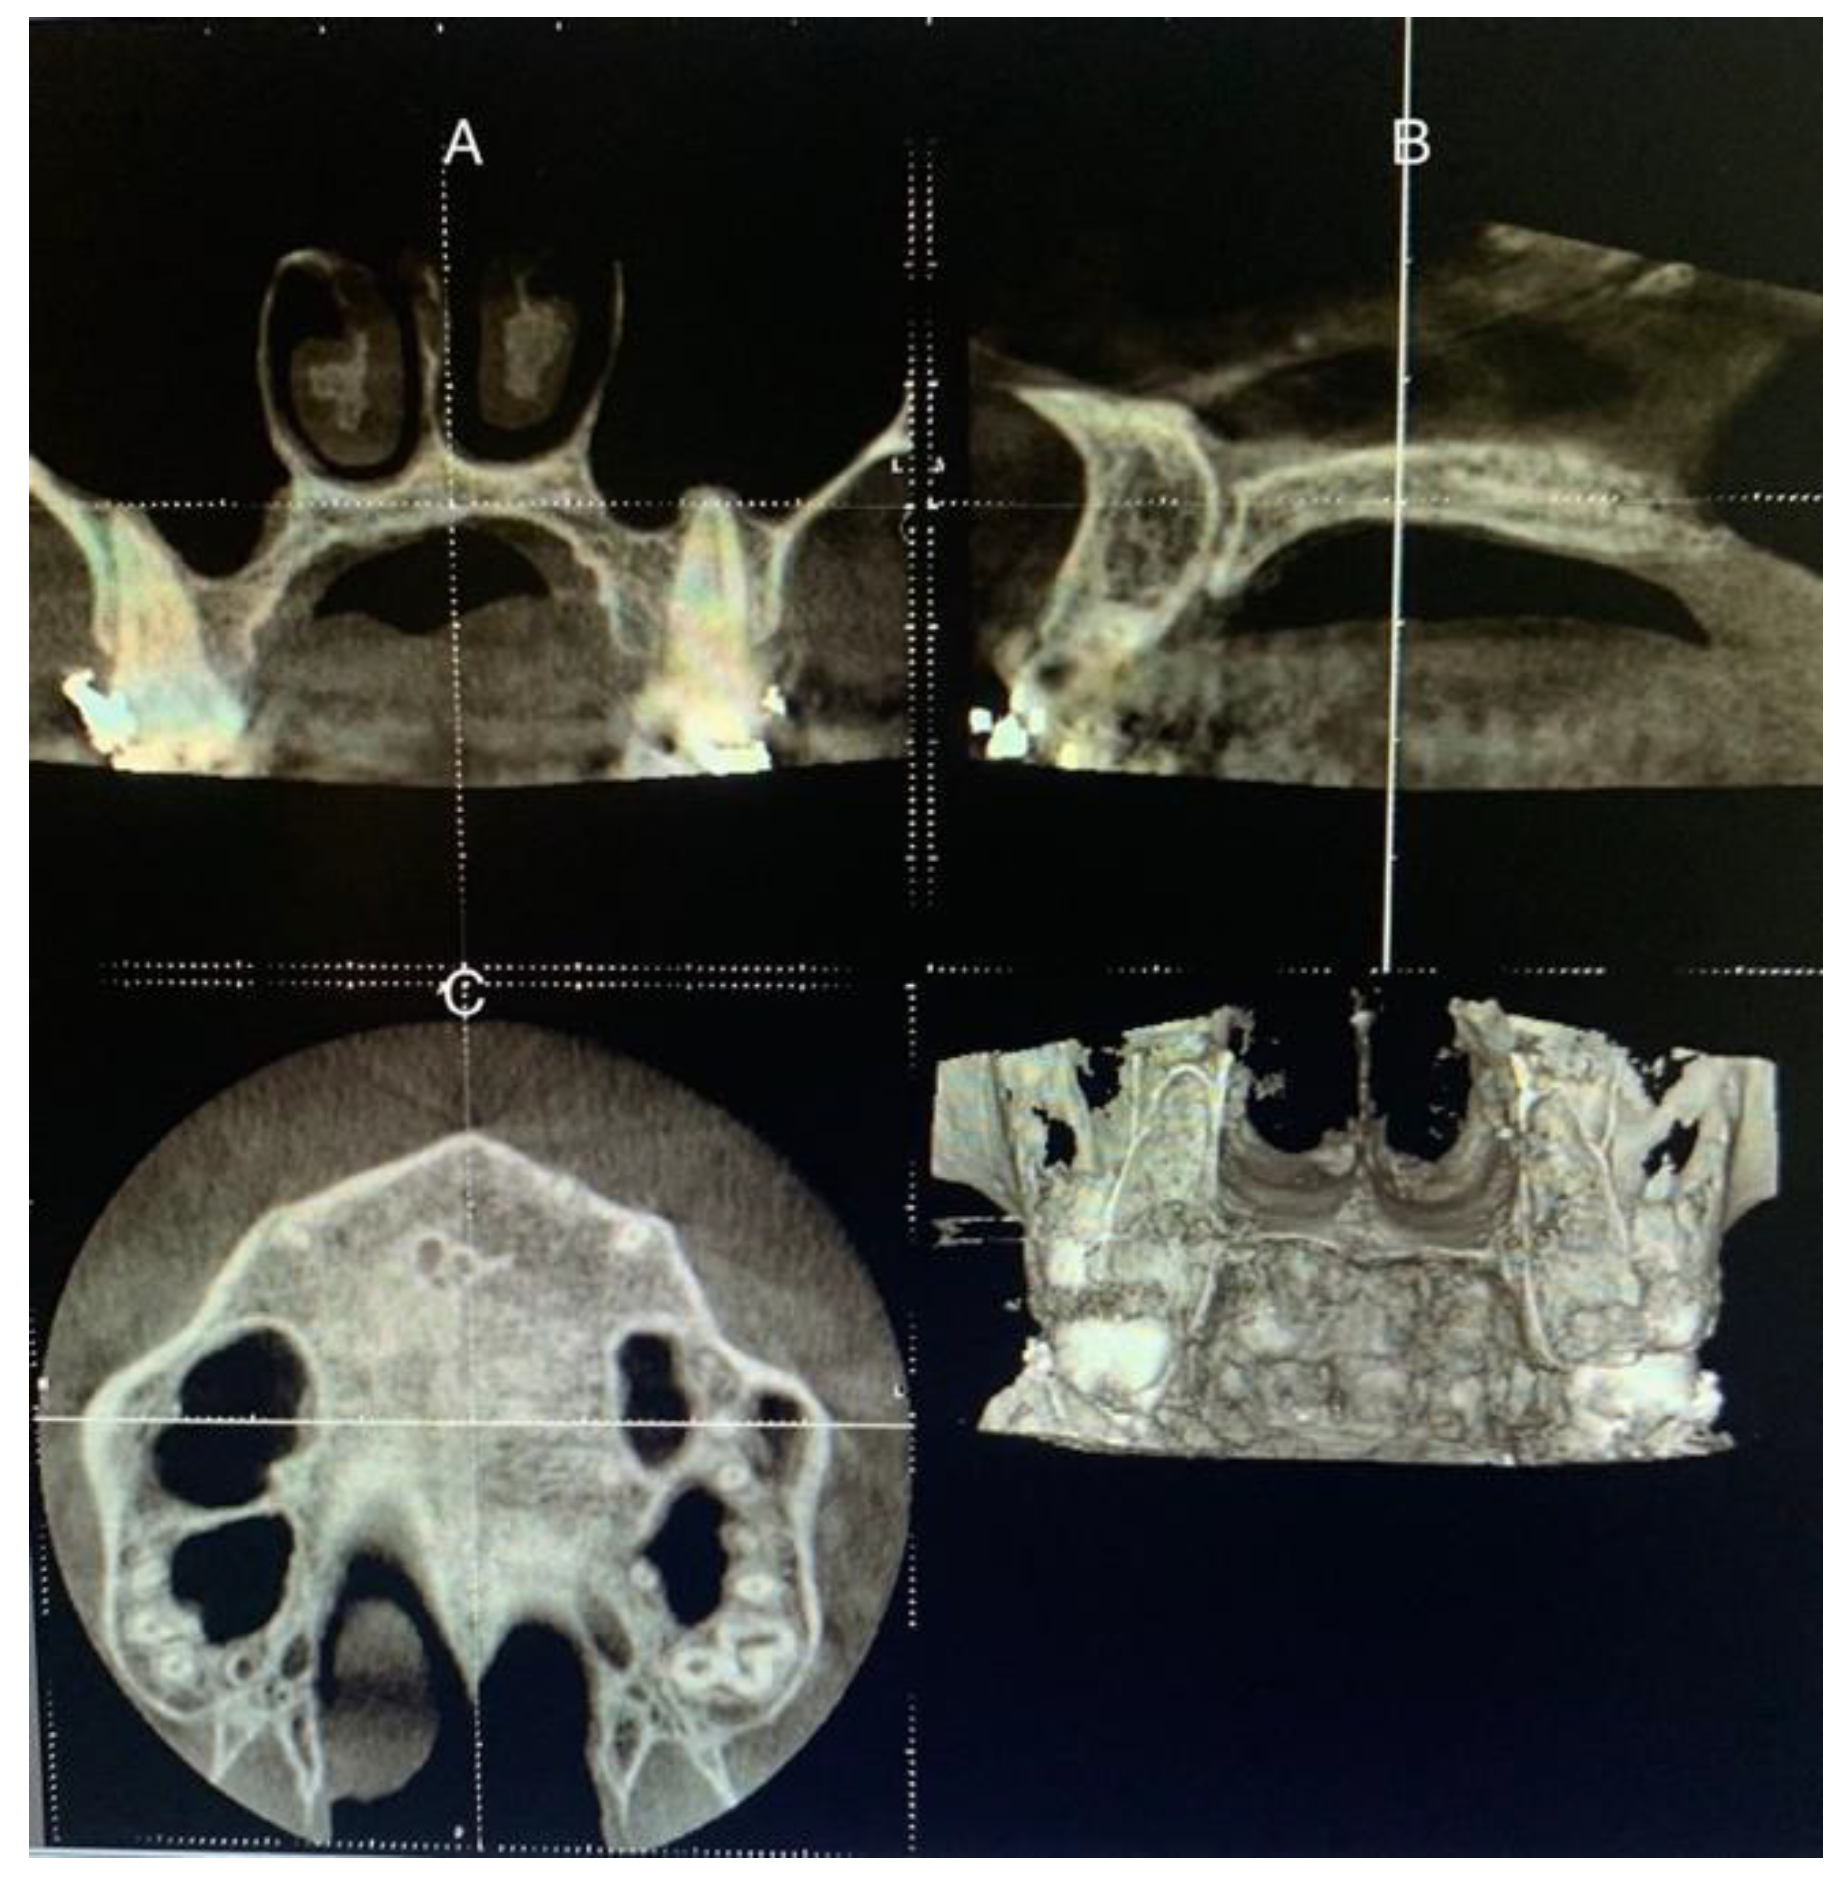

The patient’s head was positioned in the three planes of space in a standardized protocol, instructing patients to maintain the natural position of the head and to occlude with their usual maximum intercuspation. Thus, the software cursor for image analysis was placed in the patient’s mid-sagittal plane for the axial and coronal view. For the sagittal view, the patient’s head was adjusted so that the horizontal reference line matched the midpalatal region (palatal plane), which is the annular bone between the superior and inferior cortexes (Figure 2).

Figure 2.

Procedures on CBCT sections to determine the stage of maturation of the palatal suture. (A) Coronal view. (B) Sagittal view, the reference line placed on the hard palate. (C) Axial view.